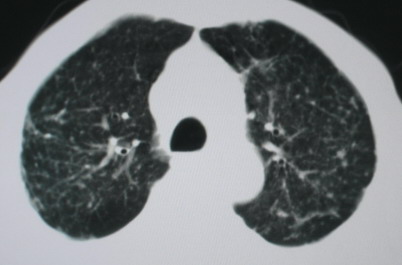

以下是引用卜一在2008-6-3 19:33:00的发言:[br]双肺结节,以双上肺分布为多,期间搀杂片状致密影及索条致密影。考虑:继发性肺结核伴血型播散可能性大。不除外肺泡ca的可能!另:椎体退变!

以下是引用panyishengct在2008-6-3 21:09:00的发言:[br]双上肺弥漫性小结节影,纵隔窗内钙化淋巴结影,考虑矽肺或/和tb可能性较大,不除外肺ca可能。腰椎考虑退变。 [br][br]